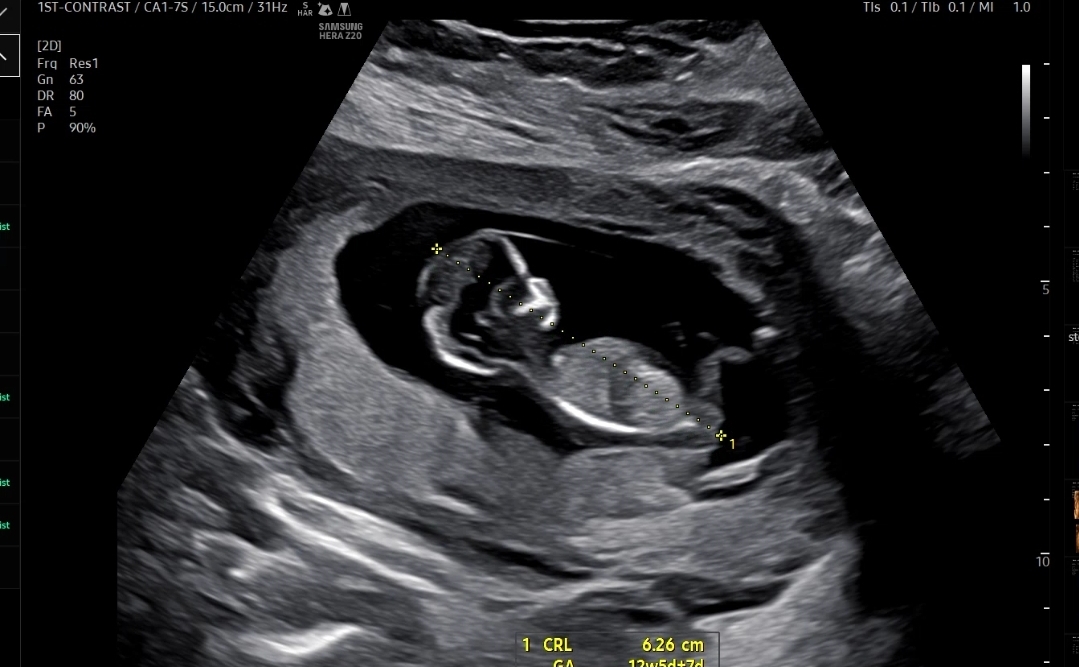

우선 아기크기와 심장소리를 확인했는데 아기크기도 6.26cm, 심장소리도 171bpm으로 잘 뛰고 있었다

처음으로 그나마 사람같이(?) 보이던 입체 초음파 ㅋㅋ

그동안 입체 초음파는 거의 사람형태가 아니어서 굳이 안 보여주셔도 되는데 싶었는데

이번에 처음으로 그나마 사람의 형태 비스무리하게 보였다